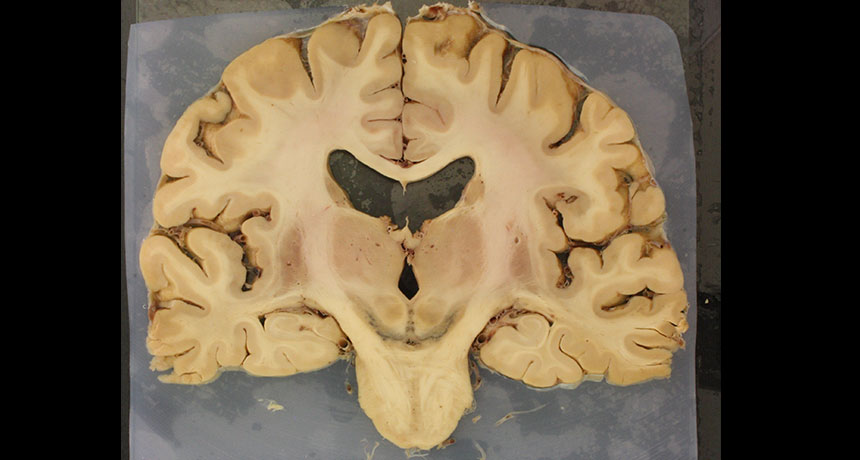

RISK FACTOR Pigmented nerve cells (black U-shape, center) in the human brain die in Parkinson’s disease, destruction that may be affected by iron levels.

Writing in the April Brain, Hare and collaborator Kay Double of the University of Sydney argue that the chemical messenger dopamine teams up with iron to form a “toxic couple” that destroys nerve cells, or neurons. This troublesome duo, with their resulting chemical products, is particularly dangerous in the substantia nigra, the dopamine-rich part of the brain damaged in Parkinson’s, Hare and Double propose.

When protective coatings that surround and protect dopamine deteriorate, or when iron levels rise, cells can be harmed by these unintended chemical reactions. And because the substantia nigra is awash in both dopamine and iron, neurons there may be exposed to an extra-large dose of 6-hydroxydopamine.

This part of the brain is packed with iron, but that abundance may be deceiving, says Tracey Rouault of the National Institutes of Health in Bethesda, Md. She argues that the substantia nigra is a natural iron reservoir that simply stores the essential element for use. “People who don’t get Parkinson’s also have iron in those areas,” she says. “No one to my satisfaction has proven that the iron is excessive.”

What’s more, those elevated iron levels seen in the substantia nigra of people with Parkinson’s may not be in the neurons themselves. Instead, iron may be packed inside scavenger immune cells called microglia, cells that gobble up damaged debris. “Our eyes are fooling us,” Rouault says. Neurons that appeared to be overfed with iron may actually be starving.